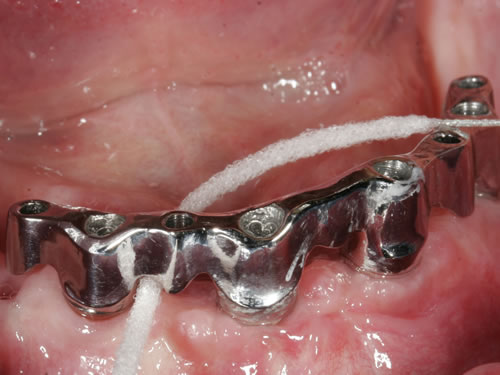

Abb. 3.7: Individuelle Stegversorgung aus Stahl auf vier Implantaten im zahnlosen Unterkiefer.

Abb. 3.8: Individuelle Stegversorgung aus Gold auf vier Implantaten im zahnlosen Unterkiefer.

Für den zahnlosen Ober- und Unterkiefer werden dies häufiger Stegkonstruktionen oder Teleskopversorgungen sein (Abb. 8.8 bis 8.16).

Abb. 8.8: Individueller Steg auf 4 Implantaten im zahnlosen Unterkiefer.